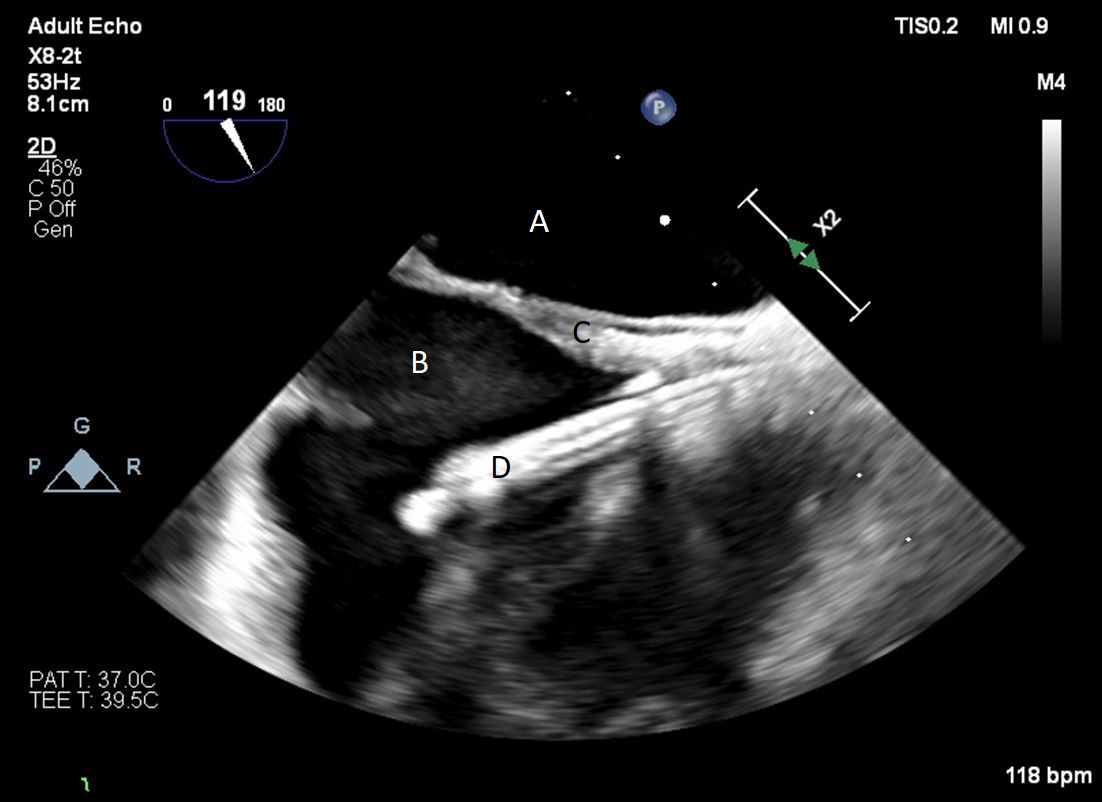

The TandemHeart Protek Duo is a percutaneous right ventricular assist device (RVAD) placed via a dual-lumen 29 French sheath in the right internal jugular vein. The inflow lumen is situated in the right atrium and outflow lumen in the main pulmonary artery. The port lumens are connected externally to a TandemHeart centrifugal pump [31]. As this is generally placed in the operating room, intra-operative TEE can be used to help guide placement. Similar to the Impella RP, bicaval and midesophageal 4 chamber views can visualize the inflow cannula and RV inflow-outflow view and upper esophageal views can be used to visualize the outflow cannula (Figs. 13,14,15). On occasion, its placement can result in distortion of the tricuspid valve morphology with resultant tricuspid regurgitation (Fig. 16). If this is noted, cannula repositioning can be considered. TEE can also help in identifying the ideal pump speed for a patient on TPD support. When utilizing a “ramp protocol”, where the pump speed is progressively increased intraoperatively, midline interventricular septal position can indicate an appropriate amount of RV support [32].

Fig. 13.A bicaval view on a TEE done during placement of a Protek Duo. The inflow lumen is seen entering the right atrium from the SVC. (A) Left atrium. (B) Right atrium. (C) Interatrial septum. (D) Protek Duo inflow lumen.

Fig. 14.Color flow imaging demonstrating a mosaic pattern at the inflow port. The interatrial septum and left atrium are also visualized. Note that no blood flow is being entrained from the left atrium across the inter atrial septum. (A) Left atrium. (B) Inflow port in the right atrium. (C) Mosaic pattern at the inflow port on color flow doppler.